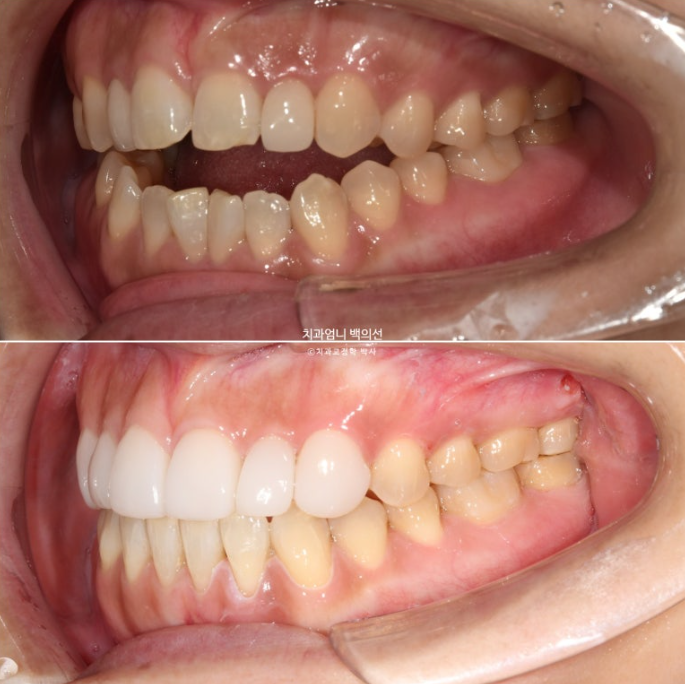

2023.05~2025.05

23.05~25.05

2년간의 치료결과 중첩을 해보면 어금니가 3mm 함입되었고 앞니가 위 아래 각각 1mm씩 정출이 되어 개방교합이 완전히 해소되었습니다.

함입된 어금니 덕에 아래턱이 더 다물리며 자가회전이 일어나서 하관이 짧아졌습니다.